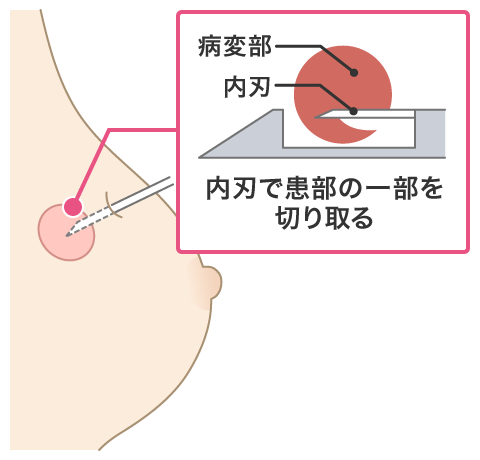

針生検(組織診)

針生検(組織診)

組織診では、専用の針を使用します。しこり(腫瘍)に直接針を刺し組織を切り取ります。局所麻酔を使用しますので、基本的に痛みは感じにくいです。細胞診に比べて組織量を多く取り出せるので、より正確な診断が可能です。検査の所要時間は20分程度です。